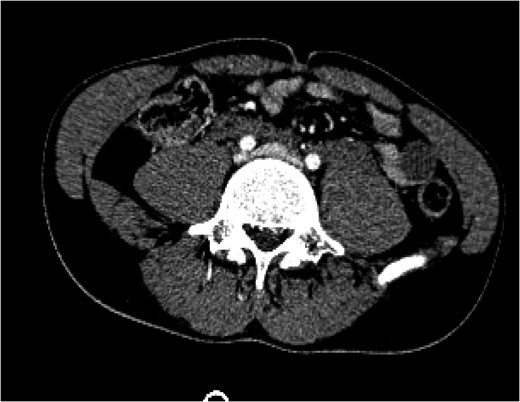

A 24-year-old man was brought by ambulance to our facility after having been involved in an unhelmeted motorcycle collision. He presented with sinus tachycardia up to 123 beats per minute, a Glasgow Coma Score of 15, and had an obvious deformity of the right lower extremity. His tachycardia improved with 2 L of crystalloid fluid bolus. He was stabilized in a cervical collar and a Sager traction splint on his right lower extremity and taken for CT scans of his head, cervical spine, chest, abdomen and pelvis as well as plain films of his extremities. According to our institutional protocol, he underwent CT angiogram of his neck given his skull base fracture. He was found to have a right kidney laceration with active extravasation, two large hepatic lacerations without active extravasation, a right midshaft femur fracture, bilateral distal radius fractures, a left occipital condyle fracture, a dissection of the left internal carotid artery, and pooling of IV contrast near the bifurcation of his inferior vena cava (IVC). This was concerning for a vena cava or iliac vein injury (Fig.

Figure 1:

A CT of the abdomen and pelvis taken on arrival (Day 1) showed a blush of contrast at the bifurcation of the common iliac veins.